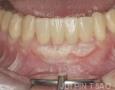

1 Months

3 Months